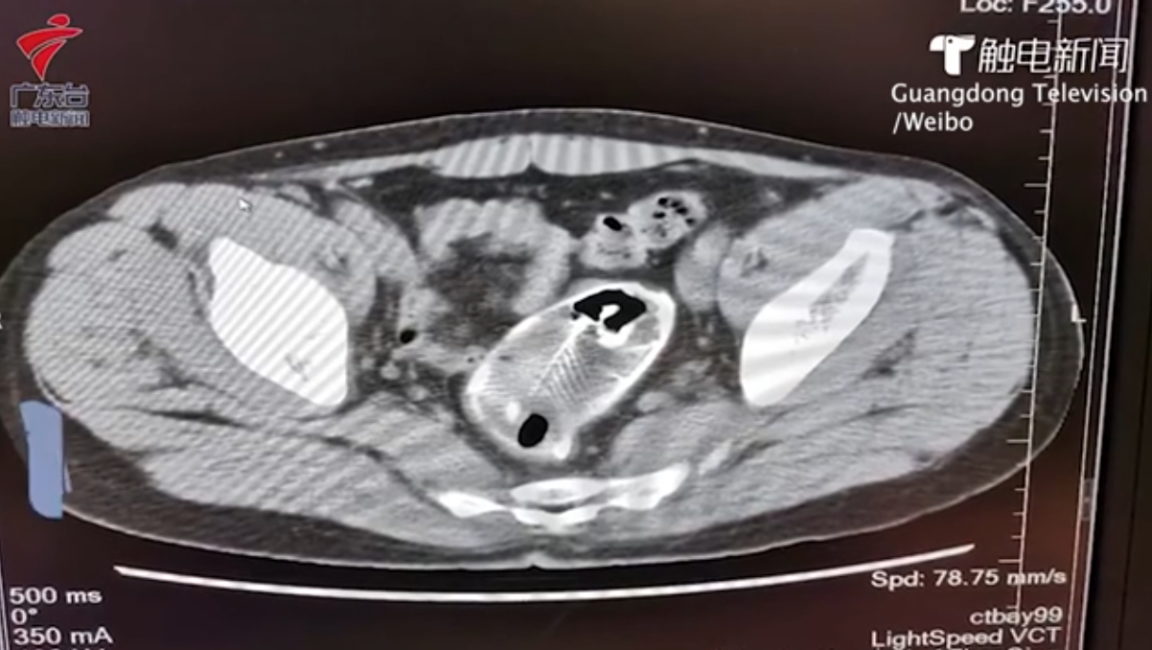

Il y a quelques jours, un homme d’une trentaine d’années est entré dans un hôpital de la province du Guangdong (Chine) en se plaignant de sévères douleurs à l’abdomen. Comme l’explique le quotidien The Shanghaiist le 8 juin 2020, les médecins ont été très surpris par les radios du corps du patient. Et pour cause, ce dernier avait un poisson dans son rectum !

Après avoir pris connaissance du problème, les médecins ont naturellement demandé au patient comment l’animal était arrivé là. L’homme a tout simplement rétorqué qu’il s’était accidentellement assis dessus. Ce qui n’était visiblement qu’une excuse n’a pas empêché les chirurgiens de pratiquer l’opération nécessaire afin d’extraire le poisson. Toutefois, les professionnels ont d’abord effectué une endoscopie filmée et diffusée en ligne sur le réseau social chinois Weibo.

Selon les médecins, le poisson n’est autre qu’un tilapia du Mozambique (Oreochromis mossambicus). Or, cette espèce peut mesurer jusqu’à près de 40 cm ! Heureusement pour le patient, le poisson coincé dans son rectum était bien plus petit. Toutefois, les nageoires dorsales du poisson, composées notamment d’épines, ont endommagé les intestins du malheureux.